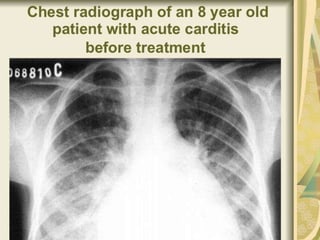

•Cardiac investigations

Electrocardiogram (ECG or EKG)

Echocardiography

 Patient with fever, active arthritis or active carditis

Investigations • Throat swab Culturedfor streptococcus group A • Serological test Anti streptolycin O titer> 250 U • Non specific indicators of inflammation ESR and C- reactive protein elevated, leukocytosis •Cardiac investigations Electrocardiogram (ECG or EKG) Echocardiography